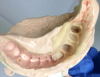

Figure 7: Preoperative triple tray impression of two teeth for which a bridge is planned shows an edentulous space between the two future abutments.

Figure 7

Figure 8: Same preoperative impression in Figure 7; edentulous space was cut out with a scalpel blade to create space for temporary restoration material to form the temporary bridge pontic.

Figure 8